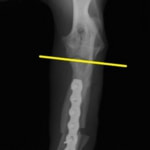

症例:柴犬 3歳

左後肢の完全挙上を主訴に来院されました。触診にて近位足根関節の過伸展を、レントゲン検査にて左足根関節周囲の軟部組織の腫脹、ストレス撮影によって距骨・踵骨と第4足根骨・中心足根骨間の脱臼および過伸展を認めました。

術中において、浅趾屈筋腱を剥離、内方へ牽引し、直接踵骨から第4足根骨までピンを挿入し(あらかじめ細いピンで下穴をあけておくとよい)、テンションバンドワイヤー法を併用し、関節軟骨の掻爬と海綿骨移植を実施しました。

術後レントゲン画像上に癒合が認められるまで約2ヵ月間は、運動を制限する必要があります。

術前正面像左関節の腫れ

左足根関節の軟部組織が腫脹しています。

術前正面像